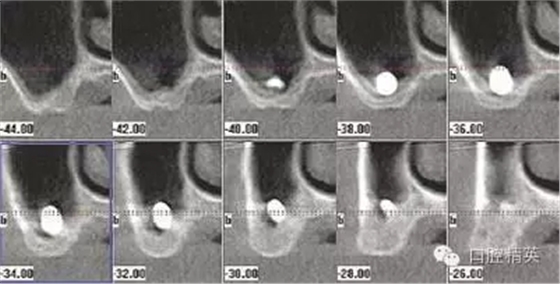

圖1b:術(shù)后ICAT三維CBCT從另外一個(gè)角度顯示種植體穿入左側(cè)上頜竇的情況

另一個(gè)和醫(yī)生僅用兩維放射線檢查造成的特殊并發(fā)癥是種植體進(jìn)入上頜竇。(圖2a-c)可能成為上頜竇異物的有牙齒,牙根,印模材料,牙科器械,近年來(lái)又增加了一個(gè)—種植體。可想而知,從上頜竇中取出異物對(duì)患者來(lái)講是創(chuàng)傷很大的。

其他研究也報(bào)道過(guò),對(duì)于這種病例,唯一的選擇是用根管顯微鏡或Caldwell Luc技術(shù)從上頜竇中取出種植體。有些文章報(bào)道了如何處理進(jìn)入上頜竇的種植體,但很少?gòu)念A(yù)防的角度來(lái)談這個(gè)問(wèn)題,其實(shí)很簡(jiǎn)單,術(shù)前應(yīng)該應(yīng)用CBCT成像檢查。